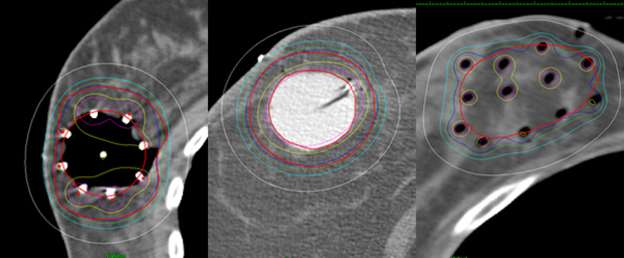

breast cancer

An axial CT scan showing the distribution of the hollow tubes (black dots) and the distribution of the targeted radiation. The white line represents a line encompassing 50% of the radiation dose. One can see how much of the skin and chest wall are spared

apbi

This is a cartoon representation of the distribution of the catheters (red) within the breast (blue) using an interstitial tube and button approach.